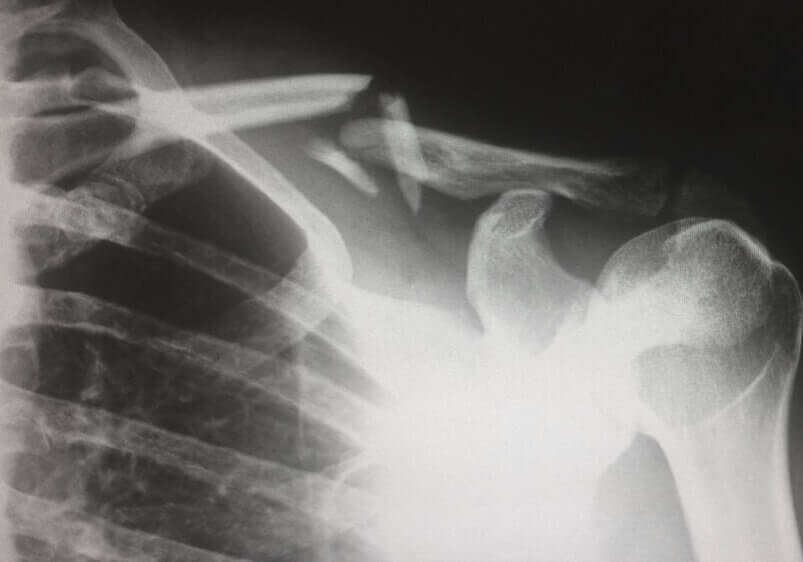

The shoulder is what is referred to as a “ball and socket” joint, much like the hip. The upper arm bone (humerus) has a rounded top end called the humeral head, where it joins with the socket-like structure (glenoid cavity) of the shoulder blade. The joint is held together by various ligaments, with cartilage in between points of friction to produce a smooth-moving shoulder.

Shoulder replacement surgery, or shoulder arthroplasty, is an elective procedure in which damaged portions of the shoulder are removed and subsequently replaced with artificial components. In almost every case of total shoulder arthroplasty, the humeral head is replaced with a metal ball, and the glenoid cavity is replaced with a smooth plastic cup. This choice of materials has proved to be incredibly effective.